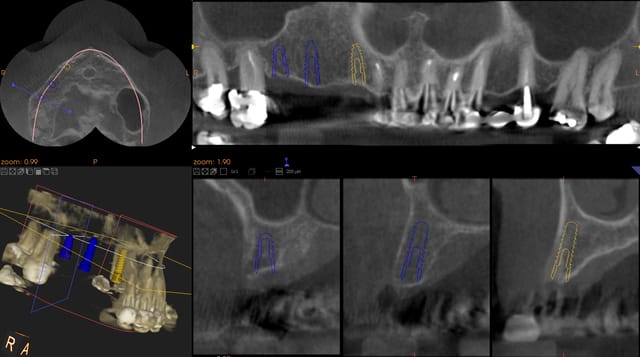

Pour continuer a manipuler le logiciel, j'ai scanné un modele avec mon cone beam kadak 9000 ( sans le logiciel correspondant, je ne l'ai pas encore, donc, au niveau reglage et precision , cela donne un modele numérique un peu "fondu" ! ).

j'ai voulu refaire une planif d'un cas posé la semaine derniere. Mon probleme risque de se trouver avec mon kodak 9000.

impossible d'obtenir une image correct avec invisaelus, qui plante une fois sur deux.

ci joint les images de ma planif kodak, du meilleur modele obtenu avec invisaelus, et du guide que j'ai pu réalisé, ( avec un defaut sur l'angle de la 12, mais je crois que patrick a un moyen de corriger le défaut sans refaire completement la base ).

Avec les artefac, le modele invisaelus est impossible a utiliser pour une planif.

je ne suis pas donc sur de pouvoir me servir de cette technique concretement :(